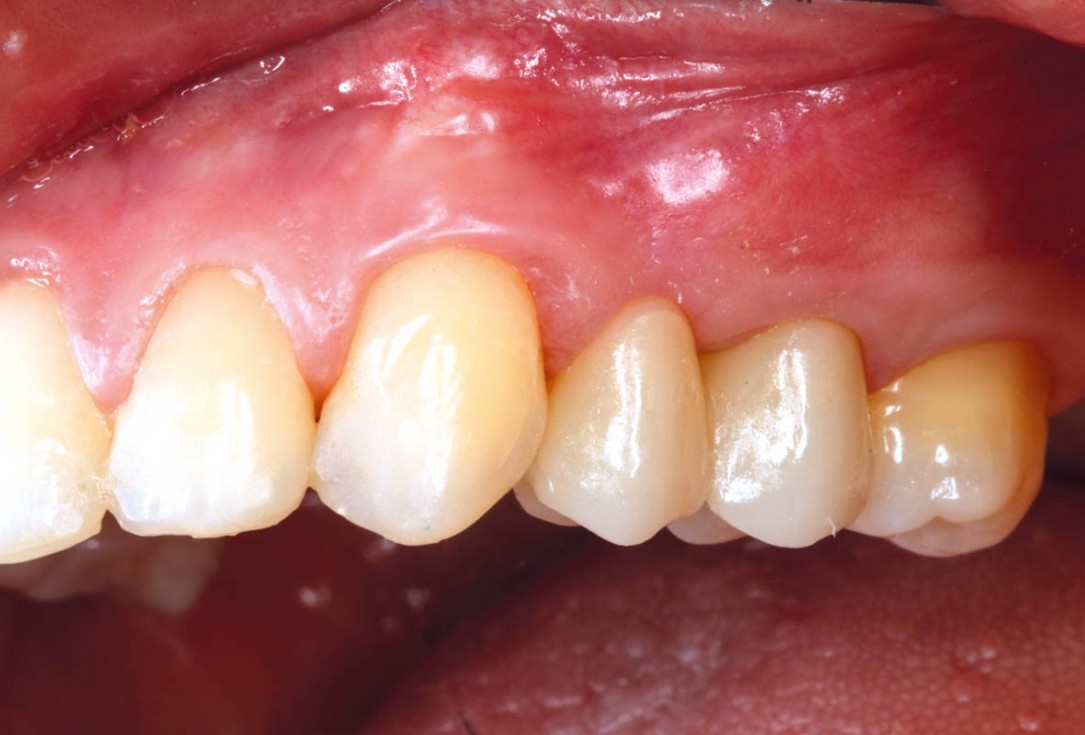

Socket seal with mucoderm® punch

Intact socket following atraumatic tooth extraction